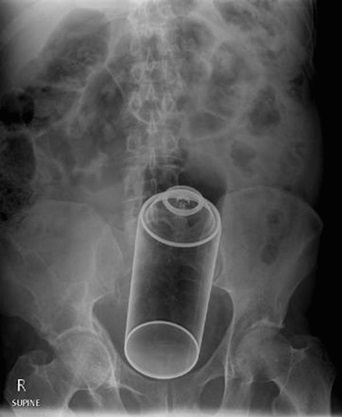

มาดูภาพเอกซเรย์ สารพัดสิ่งของที่เคยหลุดเข้าทวารหนัก

เผยภาพเอกซเรย์สุดอึ้ง สารพัดสิ่งที่เคยหลุดเข้าไปภายในทวารหนักผู้ป่วยทั่วโลก แปลกพิสดารกันจริง ๆ

การยัดสิ่งของต่าง ๆ เข้าไปในทวารหนักนั้น ไม่ว่าจะด้วยเหตุผลเพื่อหลบซ่อนการตรวจของเจ้าหน้าที่ทางการ หรือเป็นความผิดพลาดจากการแก้ขัดเมื่อเกิดอารมณ์ทางเพศก็ตาม สิ่งของที่หลุดเข้าไปนั้นล้วนแล้วแต่สร้างอันตรายให้กับอวัยวะภายในของผู้ป่วยได้หมด แต่ถึงจะเป็นอย่างนั้น เคสทางการแพทย์ว่าด้วยเรื่องของสิ่งแปลกปลอมที่หลุดเข้าไปในทวารหนักก็ยังมีให้เห็นอยู่เรื่อย ๆ ถมเถ แต่ละอย่างทำเอาอึ้ง ทึ่ง แบบไม่คิดว่ามันจะหลุดเข้าไปในทวารหนักได้จริง ๆ ดังเช่นตัวอย่างเคสที่เรานำมาฝากกันในวันนี้..

กระป๋องสเปรย์